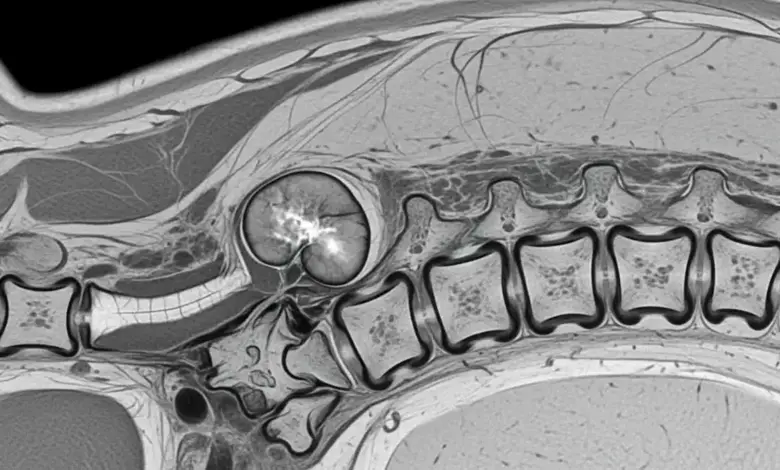

- Ressonância magnética: melhor exame para ver medula, canal vertebral, raízes nervosas e partes moles.

- Tomografia: ajuda a entender a destruição óssea e planejar a cirurgia.

- Biópsia: quando é necessário definir o tipo de tumor antes de decidir o tratamento.

Em muitos cenários, o ideal é que os exames sejam discutidos por equipe com experiência em coluna e oncologia, porque detalhes de imagem mudam condutas.